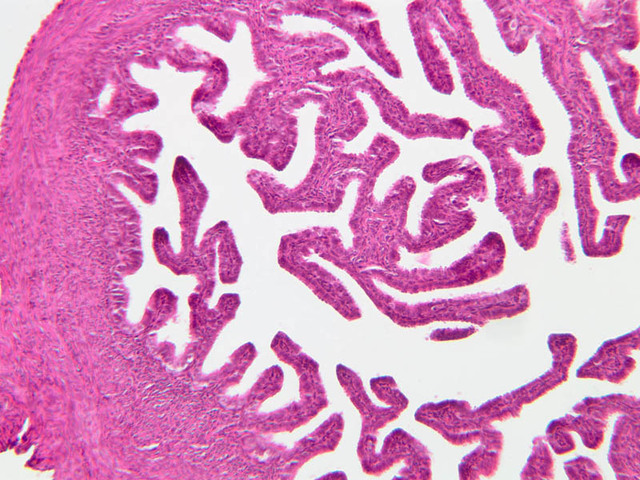

The wall of the uterine tube consists of three layers; a mucosa, a muscularis, and an adventitial/serous coat (B-96 [2.5x, 10x-labeled, 20x, 40x] [2.5x, 10x, 20x, 40x]; B-97, monkey uterus [2.5x, 10x, 20x, 40x]). The mucosa is organized into folds that vary in their degree of complexity with the tube regions. The mucosa is lined by a simple columnar epithelium consisting of two cell types, ciliated and non-ciliated, secretory (B-93 [10x, 20x, 40x-labeled]). The mucosal lamina propria consists of somewhat loose connective tissue and is highly vascular. No muscularis mucosae are present. The muscularis consists of two layers of smooth muscle, the inner being oriented in a circular fashion and the outer longitudinally.

The structure of the uterine tube is under the control of, and responds to, cyclic changes in the levels of steroid hormones. Structural alterations to provide favorable transport for the oocyte commence anew with the beginning of each cycle and peak at mid-cycle just before ovulation. These include increases in height and number of the ciliated cells as well as active secretion in the secretory cell. For the remainder of the cycle thereafter, dedifferentiation occurs. The cyclic changes occur to a greater extent in the upper ampulla and infundibulum. The margin of the infundibulum is drawn out into numerous finger-like processes called fimbrae. Microscopic examination of these will reveal that within the lamina propria are numerous large blood vessels, especially veins, as well as bundles of smooth muscle forming an intervening network. At the time of ovulation, the vessels become enlarged with blood, causing turgidity, which when combined with smooth muscle contraction brings the infundibular opening into close apposition with the ovarian surface.